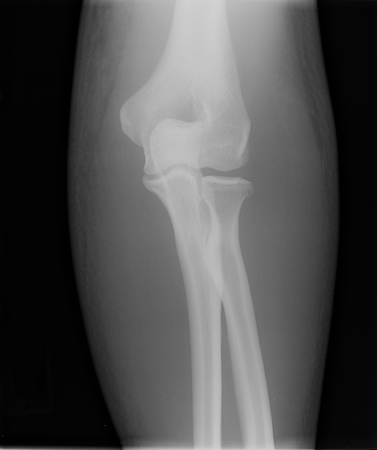

Anteroposterior x-ray view of a reduced elbow dislocation

Personal collection of Dr Paul Novakovich